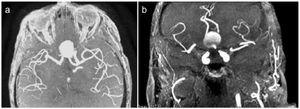

Se realiza una angio-RMN (resonancia magnética nuclear), sin contraste por su insuficiencia renal avanzada, y en ella se observa la presencia de un aneurisma sacular gigante de 19 x 16 mm en la arteria comunicante anterior (figura 1 y figura 2). Se decide tratamiento conservador, dado que los segmentos distales de las arterias cerebrales anteriores (ACA) salen del propio aneurisma y, si se emboliza o se clipa, se produciría isquemia de los territorios irrigados por las ACA.

Figura 2. Angio-resonancia magnética nuclear máxima intensidad del pixel (MIP) axial y coronal